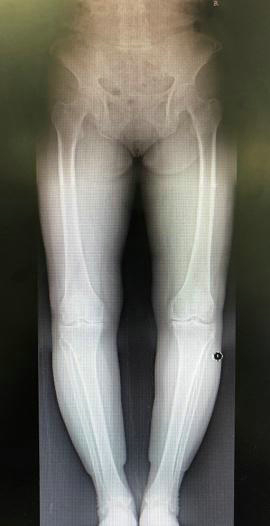

影像学检查有助于明确膝关节骨性关节炎的进展程度。X线平片检查早期可无明显异常,逐渐出现关节间隙狭窄,表明关节软骨开始变薄。开始时关节间隙在不负重时正常,承重后出现狭窄。病变后期,关节间隙有显著狭窄,而后出现骨质硬化,最后关节边缘变尖,有骨赘形成。CT及MRI检查可早期发现关节软骨及软骨下骨质的异常改变。

膝人工关节置换术前术后X线片(北京天坛医院病例)